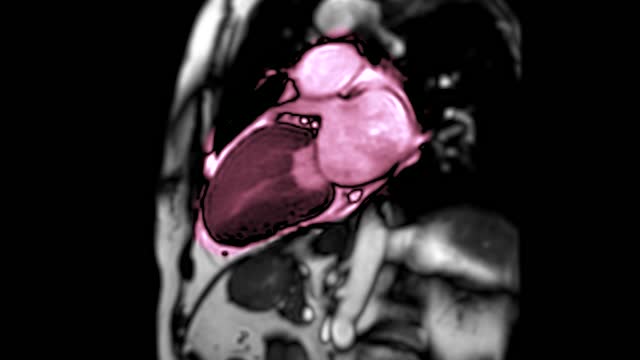

먼저, 관상동맥이라는 용어를 이해해야 합니다. 관상동맥은 심장의 혈관 중 하나로, 심장 근육에 혈액을 공급하는 중요한 혈관입니다. 이 혈관이 동맥경화라는 과정을 거치면서 석회화가 발생할 수 있습니다. 석회화란 동맥경화가 진행되면서 동맥 벽에 칼슘이 쌓이는 현상을 의미합니다. 다시 말해, 석회화가 있다는 것은 동맥경화가 오랜 기간동안 진행되었다는 표시입니다.